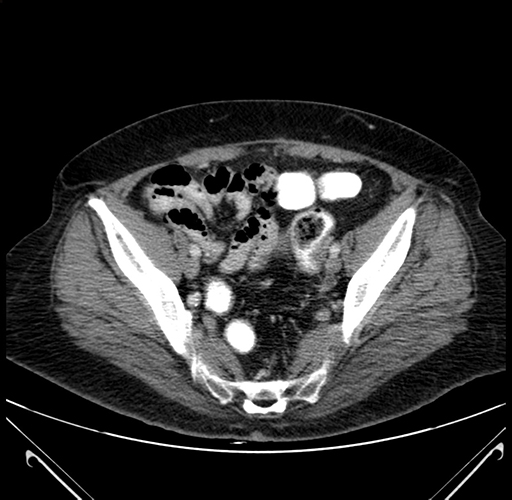

Pre-Chemo: Axial Venous

Axial Venous